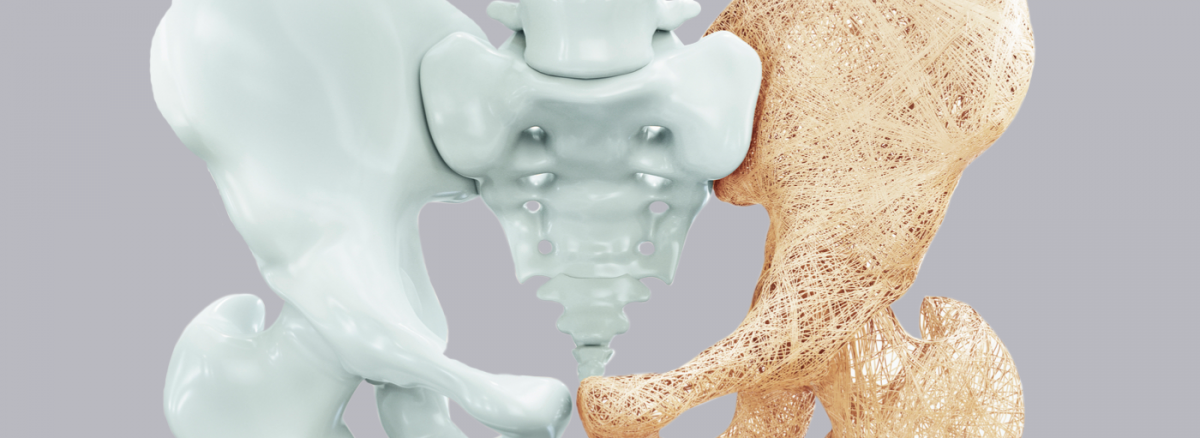

A osteoporose é uma doença caracterizada pela diminuição da massa óssea, o que faz com que os ossos fiquem mais frágeis, aumentando o risco de fratura. Essa doença é silenciosa, não sendo normalmente notados sintomas e o diagnóstico é feito, na maioria das vezes, após a ocorrência de fraturas, por exemplo.

A osteoporose é muito associado ao envelhecimento, uma vez que com o passar dos anos o organismo perde progressivamente a sua capacidade em metabolizar e absorver o cálcio, por exemplo. No entanto, alguns hábitos de vida também podem influenciar na ocorrência da osteoporose, como o sedentarismo, má-alimentação e o consumo de bebidas alcoólicas.

Essas situações fazem com que o organismo não funcione da maneira adequada, havendo um desequilíbrio entre a formação e a destruição óssea, tornando os ossos frágeis e com maior probabilidade de fraturas.